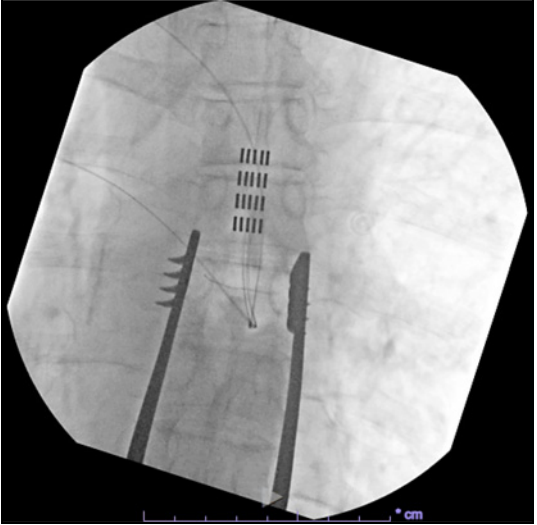

經(jīng)疼痛科行SCS臨時電極測試,于T7椎體上緣植入2根8觸點針狀電極,刺激后疼痛緩解90%,VAS降至1-3/10,遂決定行永久植入。通過T8椎板切開術(shù),在T7中段至T7上段水平植入5根4觸點針狀電極,永久刺激器埋在腰部。初始設(shè)置為:脈寬500μs及1000μs,頻率40Hz,電流1.7mA。

電極植入位置